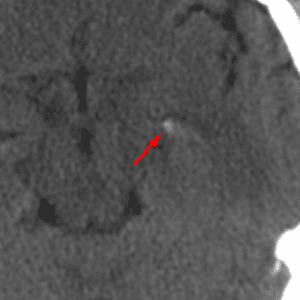

Choroid Plexus in Foramina of Luschka

Mimicking hemorrhage or a CP angle mass